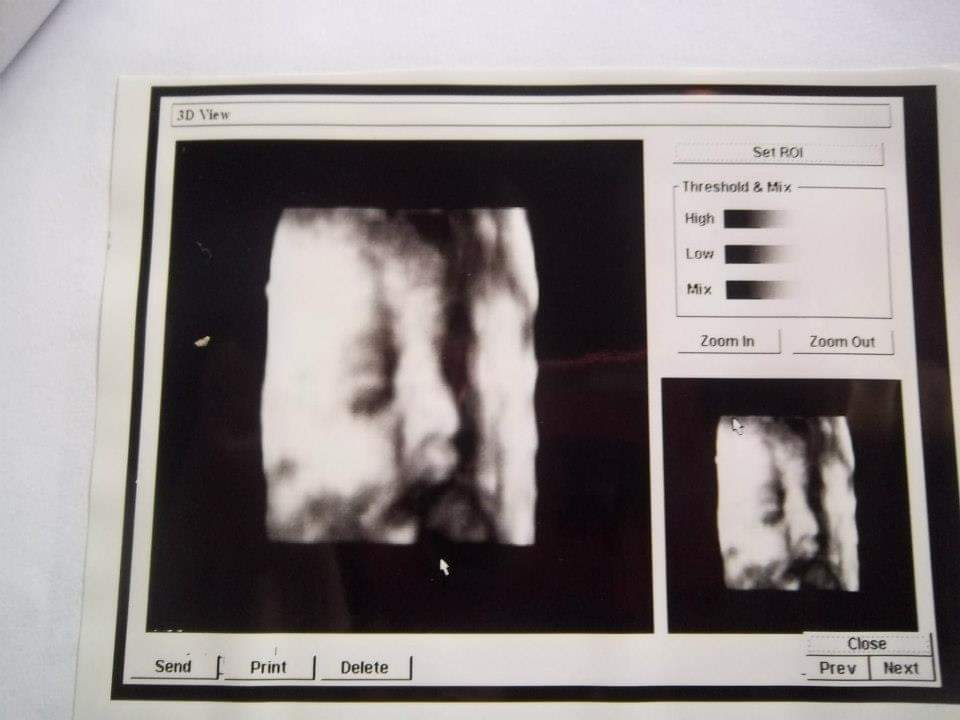

Una gran repercusión ha tenido la denuncia de Belén Aguilera Opazo, quien a través de su cuenta de Facebook acusó a un médico de Constitución, en la Región del Maule, de entregar las mismas ecografías a diversas mujeres.

“Hace un par de días por Facebook encontré una ecografía, me pareció muy conocida, la comparé con la eco de mi hija (en ese entonces me atendía el Dr. Eduardo Oliva) y son las mismas, los mismos detalles, todo”, parte su relato.

La publicación en Facebook generó que más de 30 mujeres de Constitución alzaran la voz tras darse cuenta que tenían la misma imagen de gestación de sus hijos. Por lo demás, quedó en evidencia que la práctica del doctor no sería nueva, pues los hijos de algunas de las denunciantes que recibieron la ecografía hoy tienen hasta ocho y 10 años de vida.